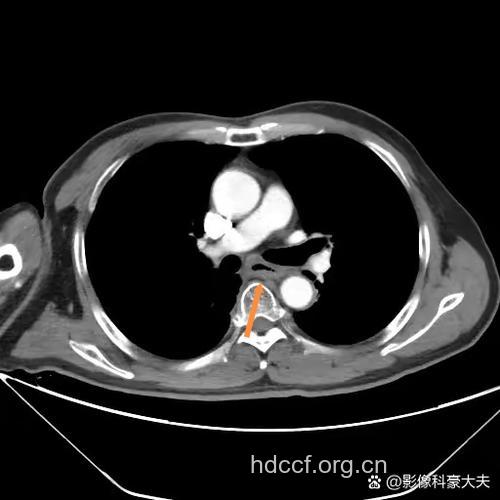

2. 二者结合可以互补应用,EUS扫描食管壁可呈现与组织学上相对应的强回声与低回声相间的5层条带结构。第1层强回声为粘膜层,第2层弱回声为粘膜肌层,第3层强回声为粘膜下层,第4层弱回声为固有肌层,第5层强回声为食管外膜。EUS可观察肿瘤侵犯到食管壁的层次。EUS判断有无癌周淋巴转移,主要观察腔外圆形低密度阴影的大小,一般大于0?5厘米的强回声团为可疑,大于1厘米者列为转移,但有一定假阳性率。